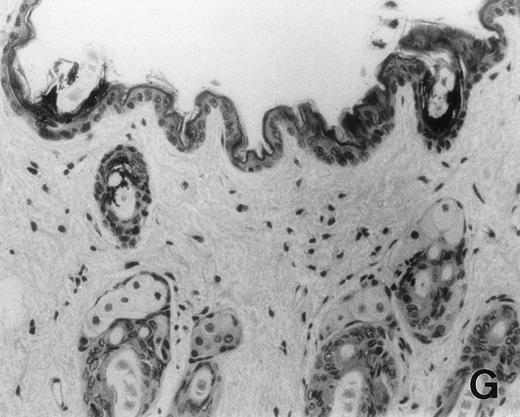

Previous in vitro studies showed that mdm100-specific, allo-restricted CTL killed H-2b tumor cells, including lymphoma cells, but not normal cells.24 However, only a limited selection of normal cells such as dendritic cells and Con-A–activated lymphocytes was available for in vitro tests. Thus, it remained unclear whether some normal tissues in vivo express sufficient levels of mdm-2 to trigger killing by the injected CTL. Several lines of evidence suggested that injected CTL did not attack normal host tissues. Firstly, none of the mice showed any acute side effects after CTL injection. Secondly, the recovery from BMT and the general health status were indistinguishable in mice that received CTL compared with control mice. Thirdly, histological analysis of liver, gut, and skin from 4 CTL treated and 4 untreated mice showed that these tissues, which are normally affected by GVHD, showed similar histology in mice with or without CTL administration (Fig 6). This indicated that CTL injection did not cause the tissue damage that is frequently seen in BMT individuals after infusion of allogeneic T lymphocytes.

Histology of BMT mice. (A through D) The histology of C57BL/6 mice transplanted with B10.A(4R) BM. One group of mice was injected with allo-restricted CTL while the control group did not receive CTL. (A) Liver from a CTL-treated mouse 3 weeks posttransplant, with no significant inflammation or necrosis. (B) Liver from a control mouse 3 weeks posttransplant, with mild periportal inflammation. Skin from a CTL-treated mouse (C) and a control mouse (D) 3 weeks posttransplant, with no significant inflammation or keratinocyte necrosis. Tissues were also examined at 4, 5, and 6 weeks posttransplant and showed no evidence of GVHD in either CTL-treated or control mice (not shown). (E-H) show the histology of (C57BL/6 × BALB/c) F1 mice, transplanted with BM from littermates. One group of mice was injected with allo-restricted CTL and a control group did not receive CTL. (E) Liver from a CTL-treated mouse 4 weeks posttransplant, with no significant inflammation or necrosis. (F) Liver from control mouse 4 weeks posttransplant, with no significant inflammation and necrosis. Skin from a CTL-treated mouse (G) and a control mouse (H) 4 weeks posttransplant, with no significant inflammation or keratinocyte necrosis. Tissues were also examined at 3 and 5 weeks posttransplant and showed no evidence of GVHD in either CTL-treated or control mice (not shown). (All H&E-stained sections, original magnification × 20.) Sections from colon and stomach also showed no significant inflammation (not shown).